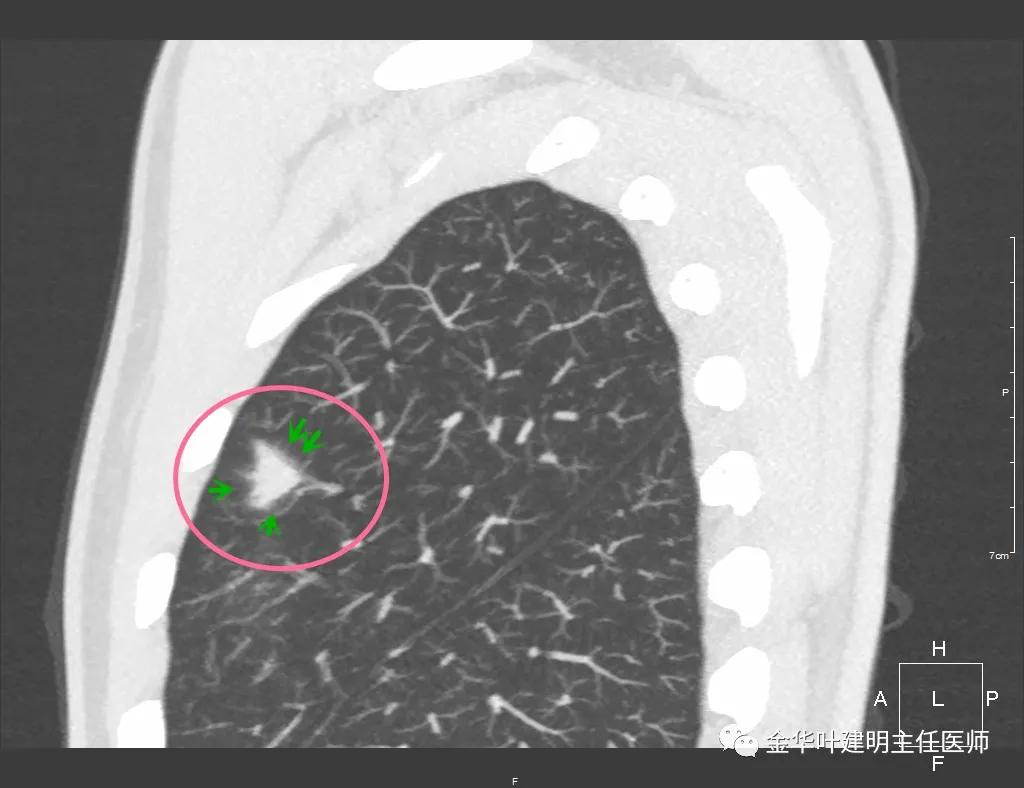

实性部分我看是有所缩小改善的,边上磨玻璃样的晕征更加明显了点

上图示病灶边缘向内凹陷,同时仍伴晕征

上图红色箭头示仍有血管进入,但蓝色箭头示边缘内凹,绿色示仍有晕征